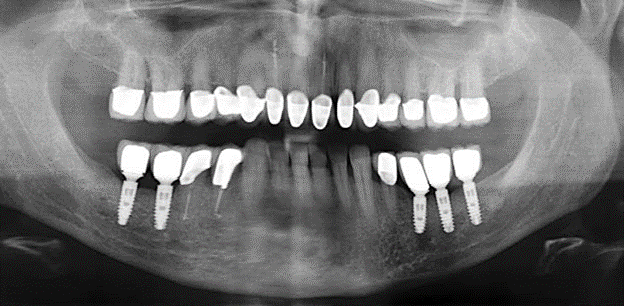

Due to the presence of periodontal disease, SPT was performed every three months in the first years following the insertion. The patient demonstrated a high degree of motivation and good compliance. The pocket depths recorded annually revealed a stable periodontal situation with a BOP index of below five per cent. On the basis of the stable periodontal situation and good cooperation on the patient’s part, the recall interval was extended to every six months as of the sixth year of the prosthetic function phase. Following the change in the recall interval, the respective annual documentation of the periodontal status continued to reveal a stable periodontal situation with no increase in the pocket depths and a BOP index below five per cent (Fig. 2a and b).

The ten-year check-up revealed no indications of advancing clinical attachment loss or peri-implant bone substance loss (Fig. 3).

Fig. 2: The pocket depths recorded annually with six-monthly SPT display no increasing trend and a BOP index of below 5 per cent with a largely inflammation-free periodontal situation. a) PERIO status in 2011 (after five years with implants). b) PERIO status in 2016 (after ten years with implants).